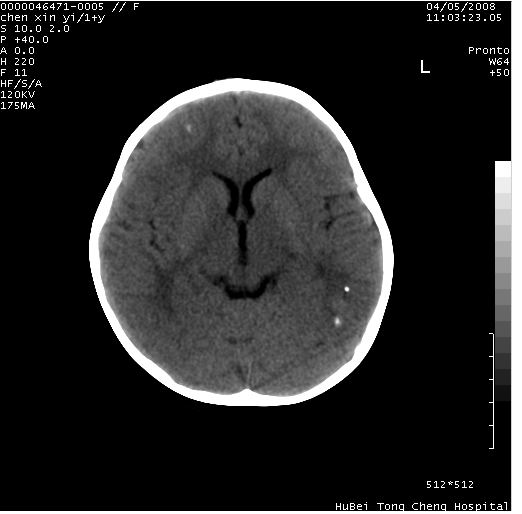

以下是引用zhangzhongshou在2008-4-9 12:54:00的发言:[br]请结合病史,有以下可能1、炎性肉芽肿钙化(含结核)2、寄生虫钙化(含脑囊虫)3、其他良性钙化性病变